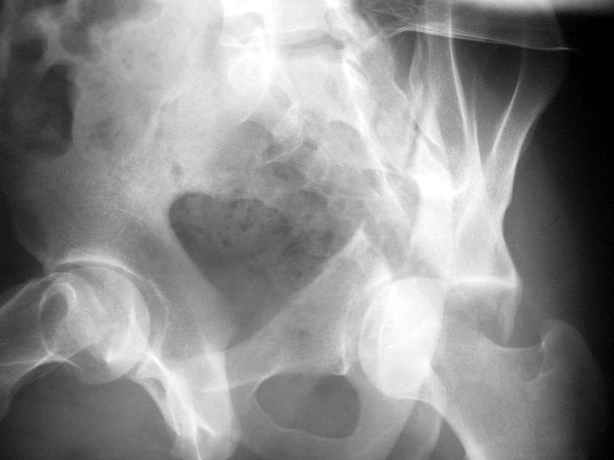

Anatoly F Lazarev 03 Сентябрь 2004, 22:39

Высылаю пример еще одного случая, остеосинтез пластиной из подвздошного доступа.

Отправитель: Djoldas Kuldjanov, M.D. 09 Сентябрь 2004, 00:43

Анатолий, во второй презентации, какой Ваш диагноз, не поперечный ли перелом ацетабулум? Вы написали, Ваш доступ был подвздошный, по моему мнению, ваш доступ лимитировал Вас к anterior column и постоянно надо было держать в контроле за натяжением femoral artery and vein, иначе грозит закупоркой артерии или вены, (были и такие experience), при сгибании в тазобедренном суставе, которое ухудшает и так ухудшенный доступ. По-моему, если доступ расширить, т.е. formal Ilioinguinal approach то применить пластину подлиннее 12-14 дырок на pelvic brim, через первое окно Ilioinguinal approach, т.е. Symphisis side, после рассечения места прекрепления muscle rectus abdominus, где достаточно места для 4 шурупов, тогда таким образом фиксированный перелом держится более стабильно и 4.5 мм шурупы для колонн можно было бы пропустить через пластину кзади впадины.